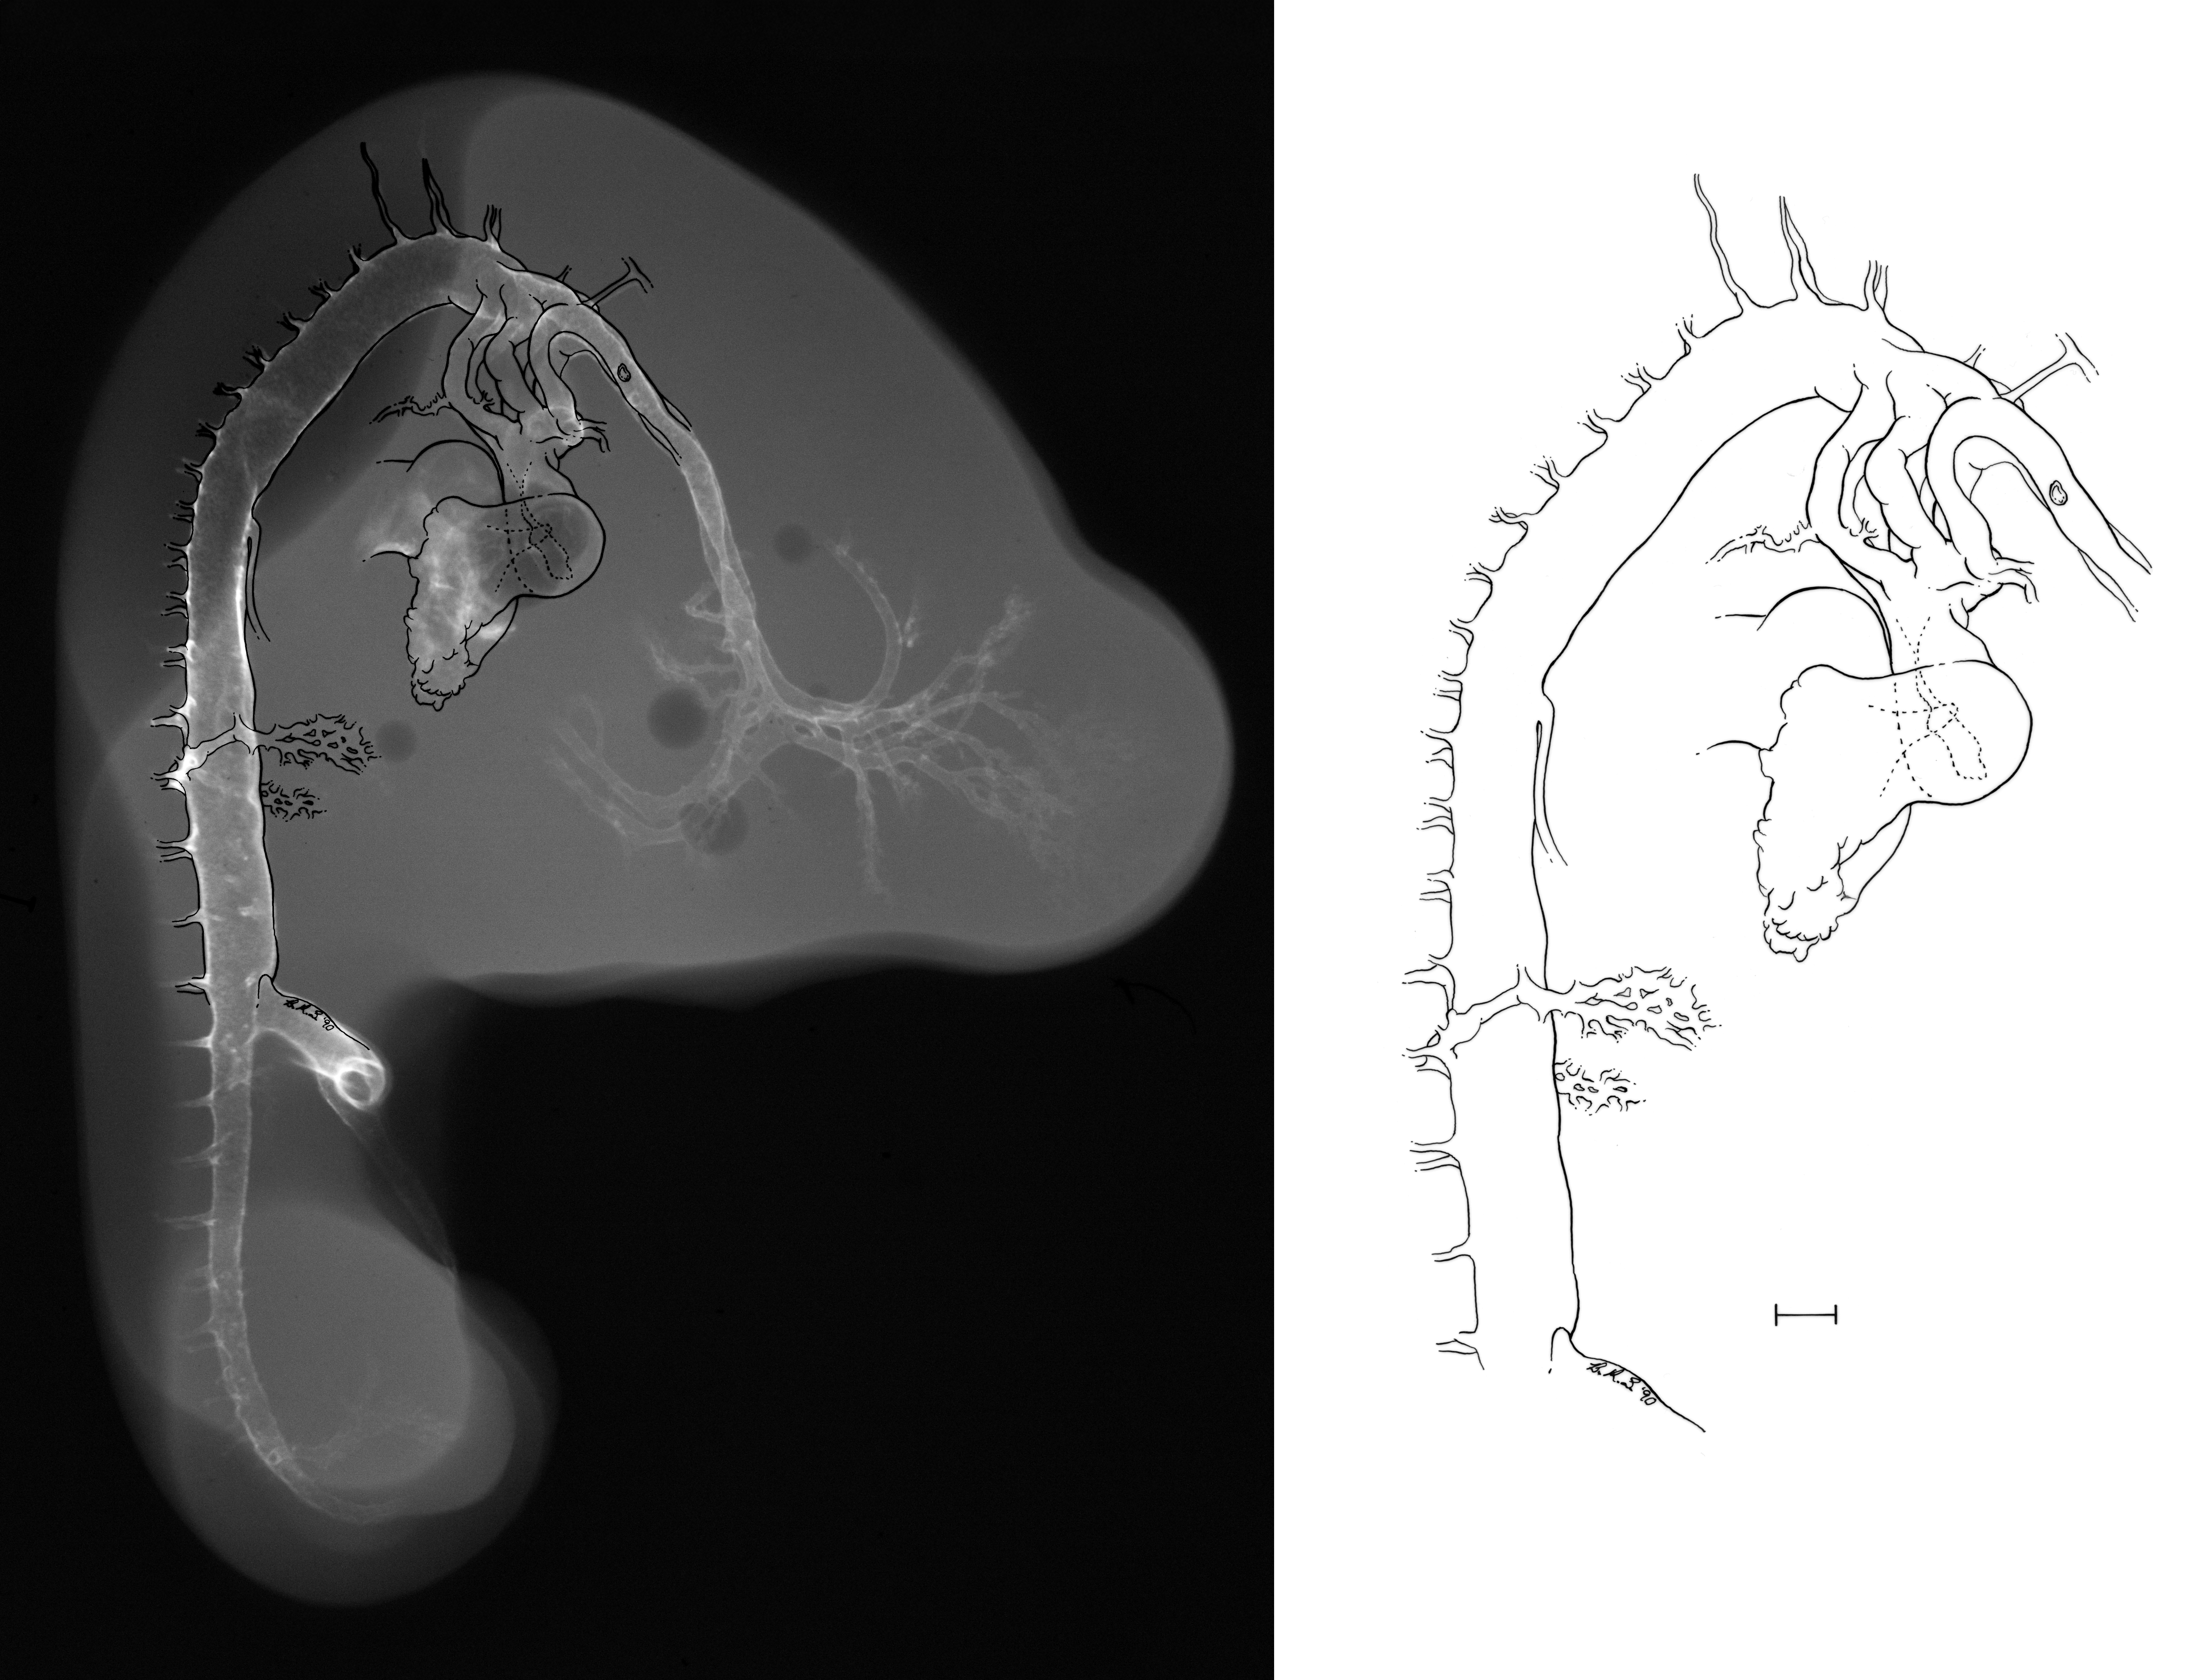

Hamburger-Hamilton (HH) Stage 23 (approx. 4 days)

X-Ray Micrographs

Drawing